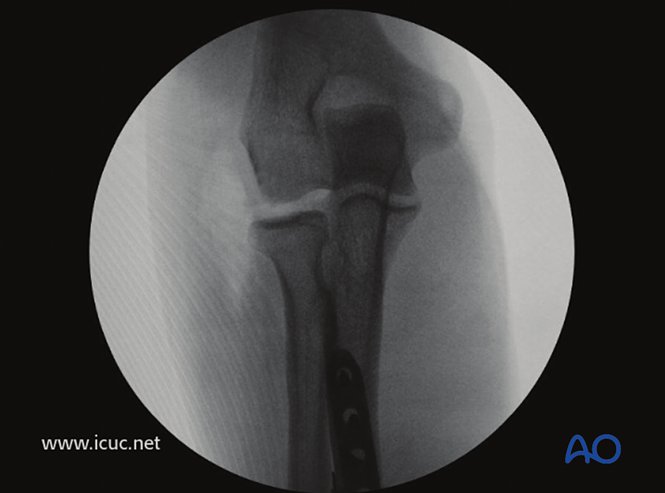

正位片显示肱桡关节复位良好。

●尺骨手术固定完成后,术者必须确认复位后桡骨头的稳定性,最好在影像增强器下进行检查。

●检查桡骨头的位置,在大多数情况下(>90%)桡骨头可自行复位。术者需确定前臂处于何种旋转位置时桡骨头最稳定。在桡骨头向前外侧脱位后,通常在完全旋后位时桡骨头最稳定。术后夹板固定时,前臂应保持在这一稳定的旋转位置。